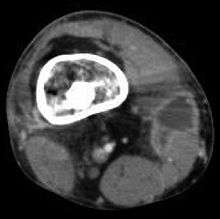

Radiographs and CT are the initial method of diagnosis, but are not sensitive and only moderately specific for the diagnosis. They can show the cortical destruction of advanced osteomyelitis, but can miss nascent or indolent diagnoses.[12]

Confirmation is most often by MRI. The presence of edema, diagnosed as increased signal on T2 sequences, is sensitive, but not specific, as edema can occur in reaction to adjacent cellulitis. Confirmation of bony marrow and cortical destruction by viewing the T1 sequences significantly increases specificity. The administration of intravenous gadolinium based contrast enhances specificity further. In certain situations, such as severe Charcot arthropathy, diagnosis with MRI is still difficult.[12] Similarly, it is limited in distinguishing bone infarcts from osteomyelitis in sickle cell anemia.[13]